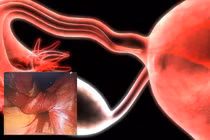

Vòi tử cung xoắn 3 vòng, tím, ứ máu và dính vào thành chậu

Khoa Phụ ngoại A5 – Bệnh viện Phụ sản Hà Nội tiếp nhận bệnh nhân nữ 41 tuổi nhập viện trong tình trạng đau bụng hố chậu trái kèm sốt.